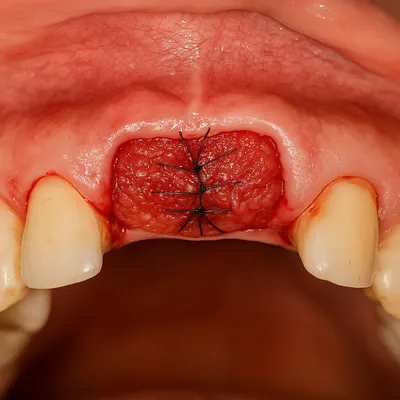

پیوند بافت نرم از کام جهت ترمیم التهاب و عقبرفتگی لثه

پیوند لثه (Gum Graft) برای بازسازی بافت نرم و پوشاندن ریشه نمایانشده.

جراحی پیوند لثه برای ترمیم عقبرفتگی و التهاب بافت دهان